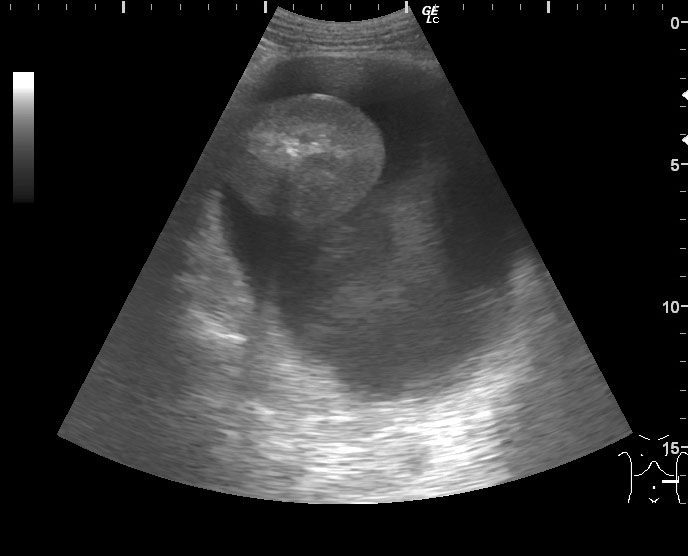

Мужчина средних лет, боли в животе, больше слева. При УЗИ панкреас изменения, характерные для острого панкреатита.

Левая почка:

Что это может быть?

Панкреонекроз хвоста поджеледочной железы с расплавлением паранефральной клетчатки слева, гнойный паранефрит, возможно, с аррозивным кровотечением.

В тот же день это скопление жидкости было задренировано. Получили прозрачную жидкость желтоватого цвета с высоченным уровнем альфа-амилазы (25000).